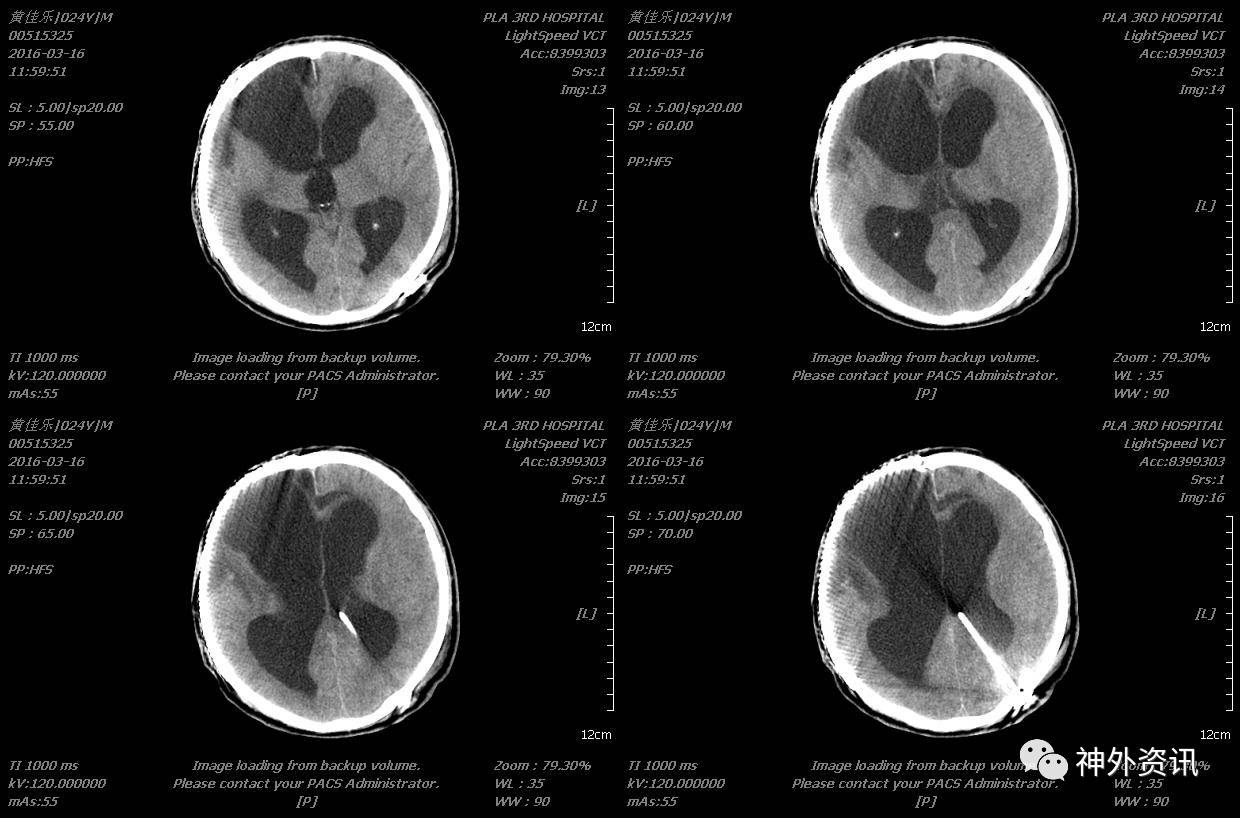

术后患者反应迟钝、大小便失禁等症状缓解不明显,于2016-03-15在全麻下行脑室-腹腔分流术,术后复查头颅(2016-03-16 11:59)示:

2016-10-11血常规:细胞25.42×109/L、降钙素原测定(PCT)0.40ng/ml,2016-10-10发现分流管处头皮水肿,行B超示:皮下组织水肿,头颅CT示较前无明显变化。腰穿检查示:无色浑浊、白细胞手工计数1958.00×106/L、中性粒细胞0.89、淋巴细胞0.11、葡萄糖(GLU)1.46mmol/L、脑脊液蛋白(PRO)0.97g/L,压颈不通畅。考虑颅内感染,再次建议家属行分流管取出术,2016-10-14行分流管取出术,术后行导管细菌培养及图片未发现细菌,2016-10-17脑脊液细菌图片:偶见革兰氏阴性杆菌,但培养未发现细菌,继续给予万古霉素、美罗培兰抗感染至3次脑脊液基本正常后于2016-11-12停药,患者逐渐恢复,意识清楚,言语清晰。

2016-10-15复查头颅CT示:拔出引流管后未见脑室继续扩大。

胸部情况较前明显好转,于2016-12-01再次复查头颅CT示未见脑室进一步扩大。

后患者逐渐康复,未再行脑室腹腔分流术,耐受良好,于2017年3月复查头颅CT未见脑室明显扩大,意识清楚,言语清晰,对答切题,扶物下可自主行走,生活大部分基本自理。

2017-03-30头颅CT示: